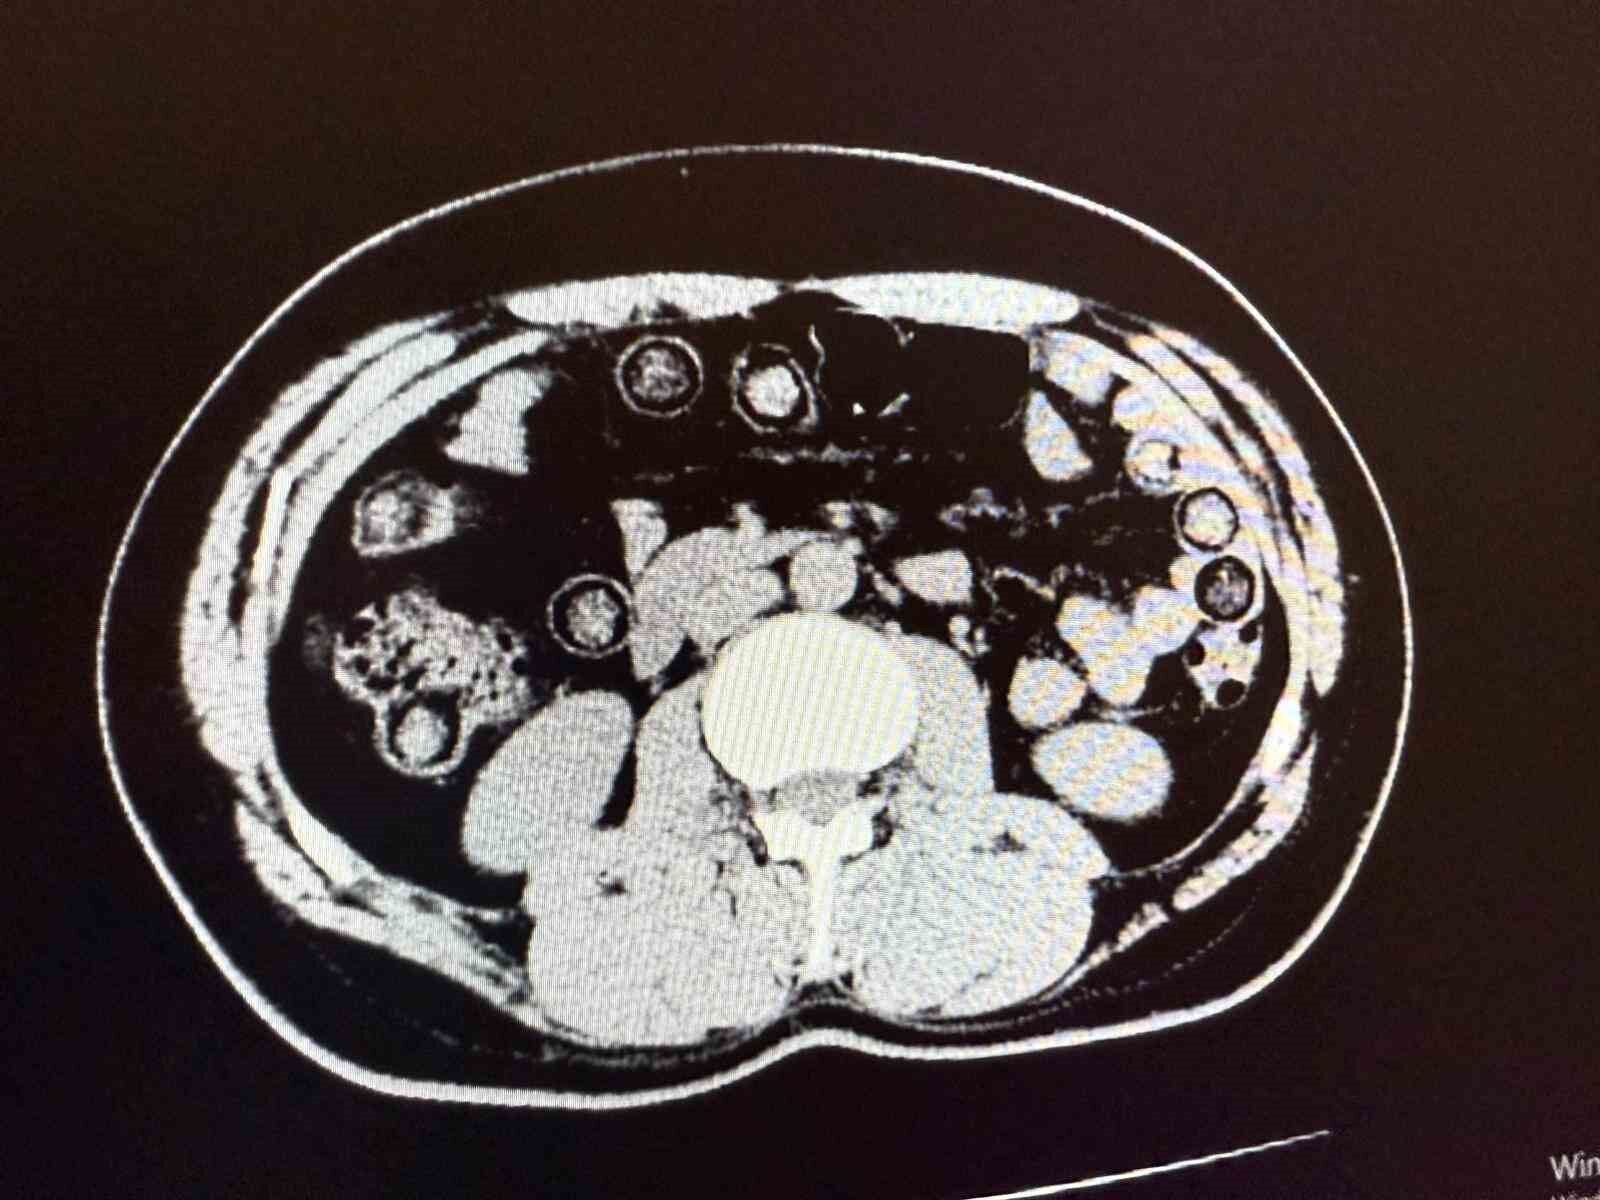

Muş Valiliği tarafından yapılan açıklamada, “Narkotik Suçlarla Mücadele Şube Müdürlüğümüzce uyuşturucu madde sevkiyatına engel olmak için yapılan çalışmalar neticesinde İran uyruklu 2 şahsın şehirlerarası yolcu otobüsü ile illere uyuşturucu madde nakli gerçekleştirebilecekleri değerlendirilmiş, 6 Aralık günü saat 11.30 sıralarında şüpheli şahısların görevlilerimizce yapılan sorgulamasında uyuşturucu madde naklettikleri yönünde kuvvetli şüphe oluşmuştur. Hastanede yapılan iç beden muayeneleri sırasında çekilen tomografi görüntülerine göre uyuşturucu madde yuttukları tespit edilmiştir. Hastanede yapılan tespit sonrasında şahısların midelerinde toplam 94 adet kapsül içerisinde daralı ağırlıkları 928 gram gelen metamfetamin maddesi ele geçirilmiştir. Şüpheli şahıslar hakkında ‘uyuşturucu ve uyarıcı madde ticareti’ suçundan işlem yapılmak üzere Cumhuriyet Başsavcılığına intikal ettirilmiş ve çıkarıldıkları mahkemece tutuklanmışlardır” denildi.